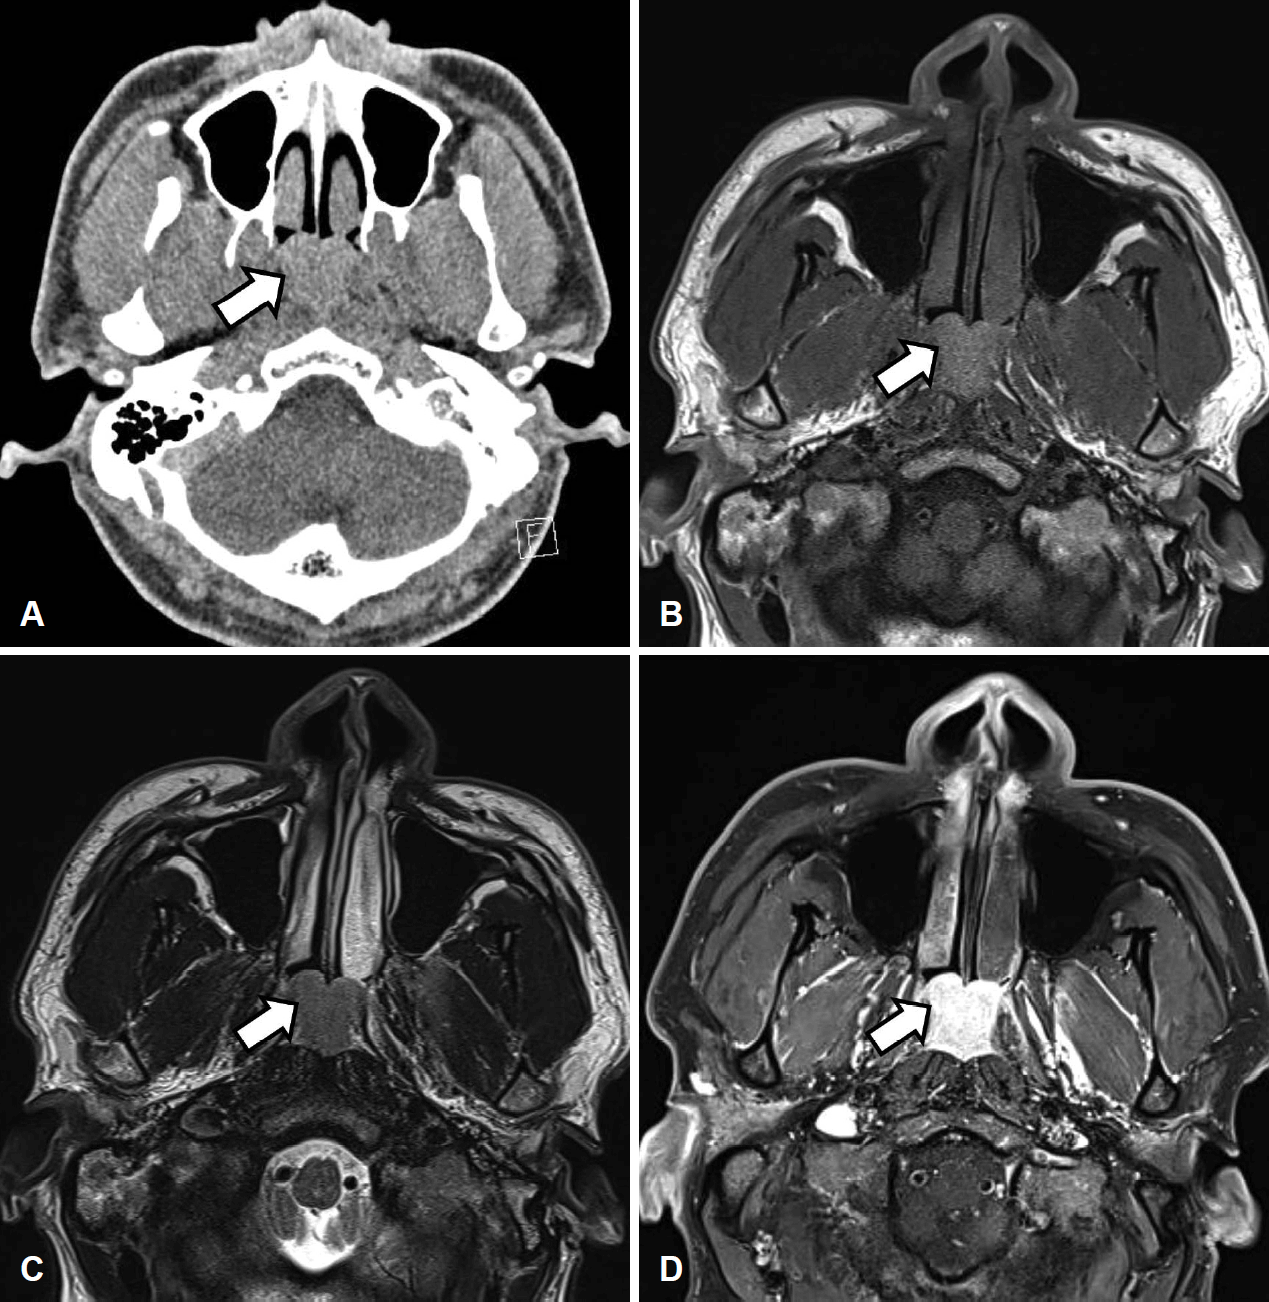

45세 남자 환자가 내원 20년 전부터 시작된 양측 코막힘 주소로 내원하였다. 콧물 및 후비루는 없었으나 코골이, 구호흡, 수면 무호흡증을 호소하였다. 시행한 코 내시경 검사상 우측으로 편위된 비중격 소견 및 양측 후비공을 완전히 막고 있는 부드러운 표면을 가진 비인두 종물이 확인되었다. 조영증강 전산화단층촬영 영상에서는 좌측 접형동의 부비동염과 함께 조영 증강되는 약 2.5 cm의 비인두 종물이 확인되었다. 이후 시행한 조영 증강 자기공명영상에서는 비인두 종물이 T1, T2 강조영상에서 모두 고강도 신호로 나타났으며, 조영증강 시 균질하게 조영 증강되어 양성 림프구 증식증, 림프종, 악성 종양 등이 의심되었다(Fig. 1). 이에 부비동 내시경 수술, 비중격 교정술 및 비인두 종물 절제 수술을 계획하였다. 수술장 소견상 매끈하고 둥근 모양의 비인두 종물이 확인되어 내시경적 절제술을 시행하였고 수술 시 종물을 겸자로 잡으면 잘 부서지고 출혈이 잘 되는 소견이 있어 piece meal로 제거하여 지혈하였다(Fig. 2). 수술 과정에서의 특별한 합병증이나 수술 후 후유증 없이 잘 회복되어 퇴원하였다.

Preoperative imaging study of the nasopharyngeal lesion. A: Contrast-enhanced CT image shows about 2.5 cm enhancing mass (arrow). B: MRI T1 weighted image shows well-defined hyperintensity mass (arrow). C: MRI T2 weighted image shows well-defined mass with high-signal intensity (arrow). D: MRI T1-enhanced image shows homogenous enhancing mass (arrow).